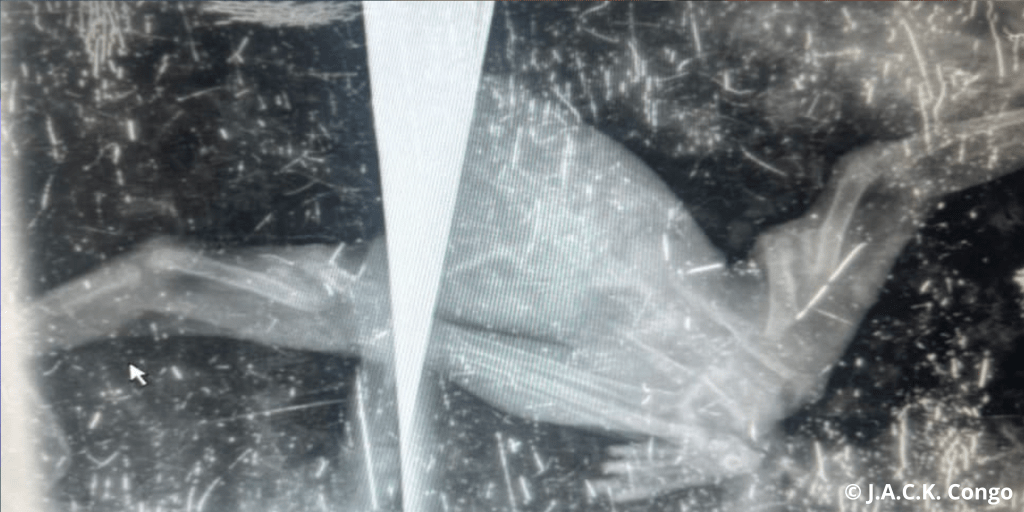

En effet, dès que nous avons remarqué des problèmes de motricité chez Buta, nous n’avons pas hésité à lui faire passer une radio. Les résultats ont révélé que l’os fracturé (fémur) s’était calcifié mais que les deux parties s’étaient soudées ensemble en se superposant. D’après le spécialiste consulté, il faut absolument casser la partie calcifiée pour mettre l’os en place à l’aide d’une broche. Si nous n’intervenons pas, Buta développera d’autres pathologies liées au système nerveux par exemple et ne marchera jamais convenablement.